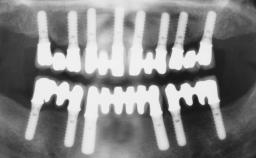

Immediate Loading of Six Implants in the Maxilla and Final Restoration with a Full-Arch Gold/Ceramic FDP Involving the Concept of Tilted Implants

# of Implants 6

Type of Implants One-Piece|Reduced-Diameter